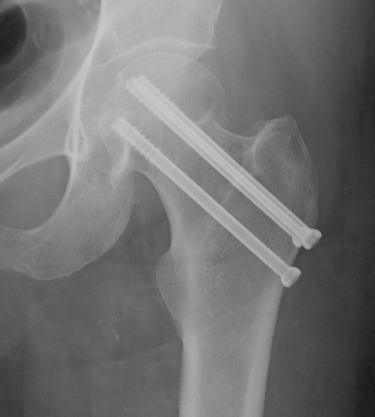

Cannulated screws

Technique

Lateral on traction table

- adequate reduction / no varus

- small incision or percutaneous

- 3 screws

- ensure inferior screw entry point is above lesser trochanter to prevent fracture

- ensure threads cross fracture site entirely to obtain compression

- need correct screw length so screw head can compress against cortex